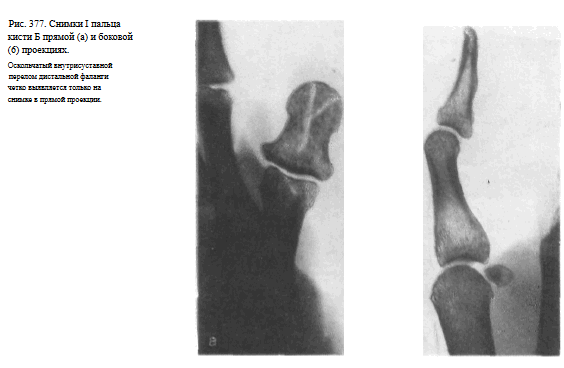

Снимок I пальцакисти в прямой тыльной проекции.

I палец прилежит к кассете тыльной поверхностью. Кисть и предплечье максимально ротированы кнутри. Для фиксации кисти в заданном положении больной удерживает ее здоровой рукой.

Используют кассету размером 13X1 8 см, перекрывая ее поперек листом просвинцованной резины.

Пучок рентгеновского излучения направляют отвесно на проекцию пястно-фалангового сустава (рис. 373).

На рентгенограмме видны фаланги и частично I пястная кость, их медиальные и латеральные поверхности, рентгеновские суставные щели пястно-фалангового и межфалангового суставов, бугристость дистальной фаланги (рис. 374).

Снимок I пальца в боковой проекции. I палец прилежит к кассете лучвым (наружным) краем.

Остальные пальцы слегка согнуты, опираются концами на перекрытую листом просвинцованно резины уже проэкспонированную половину кассеты.

Пучок рентгеновского излучения направлен на проекцию пястно-фалангового сустава (рис. 375).

На рентгенограмме выявляются тыльная и ладонная поверхности фаланг и частично I пястной кости.

Видны наслаивающиеся друг на друга сесамовидные кости рядом с головкой I пястной кости (рис. 376). Снимки необходимо выполнять в двух взаимно перпендикулярных проекциях (рис. 377, а, б).